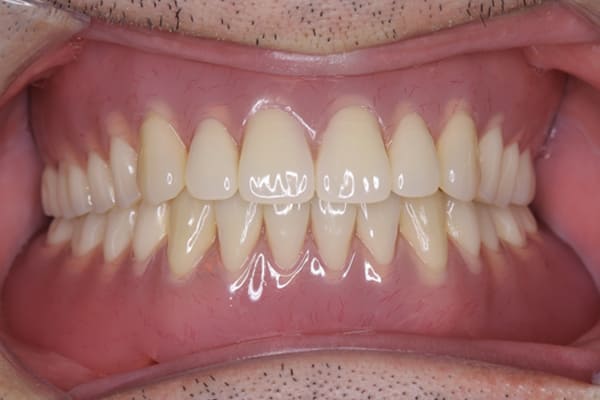

治療前後の口元の比較

こちらは、口を少し開いた時の治療前と治療後の

口元です。

正面から見た時にクラスプが目立たないように、

歯ぐきになじむ素材にて入れ歯を製作し、痛くなく自然に馴染み快適に生活を送れるようになりました。